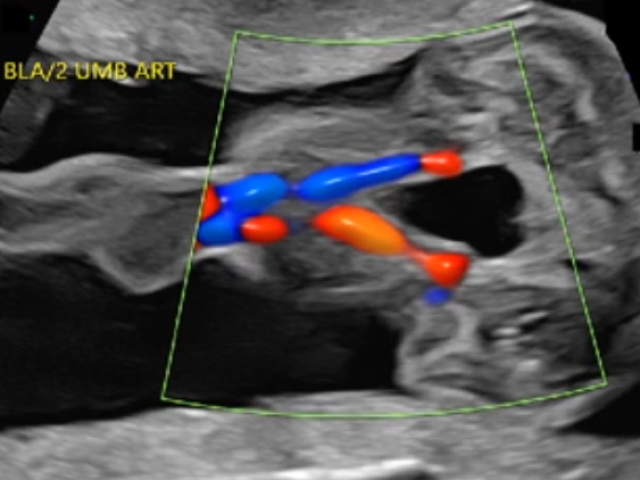

Middle Cerebral Artery, Major Malformations, Fetal Pelvis (9 CMES) $13.49 Click Here

Twins, Placenta, Fetal Growth, and 1st Trimester (7 CMES) $13.49 Click Here